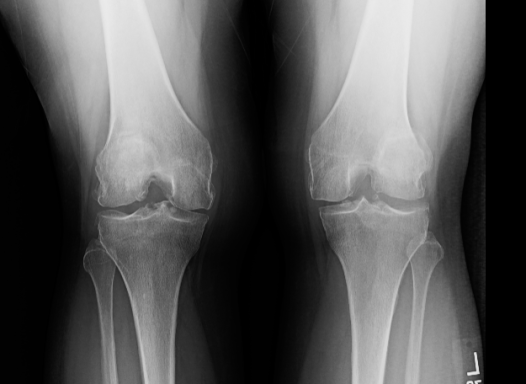

In this series, medical scans—MRI images, X-rays, and other diagnostic views—are transformed into intimate portraits that merge the clinical with the deeply personal. Each work intertwines medical imagery with biographical details, creating a layered visual narrative that honors both the physical realities of illness and the inner lives of those who endure them.

The exhibition features representations of conditions such as multiple sclerosis, lung cancer, hip and knee replacements, a broken wrist, miscarriage, and heartache—each one a story of endurance, adaptation, and faith. The artist wishes to express her gratitude to the patients and their families who entrusted her with creating artworks as unique and special as they are while acknowledging that recovery is never an individual journey; it extends to loved ones who must also heal, grieve, and rediscover vitality in the face of loss or uncertainty.

Mixed media pieces of art derived from the combination of medical scans, surveys from family and friends and genuine creativity from the creator, these artworks are one of a kind.